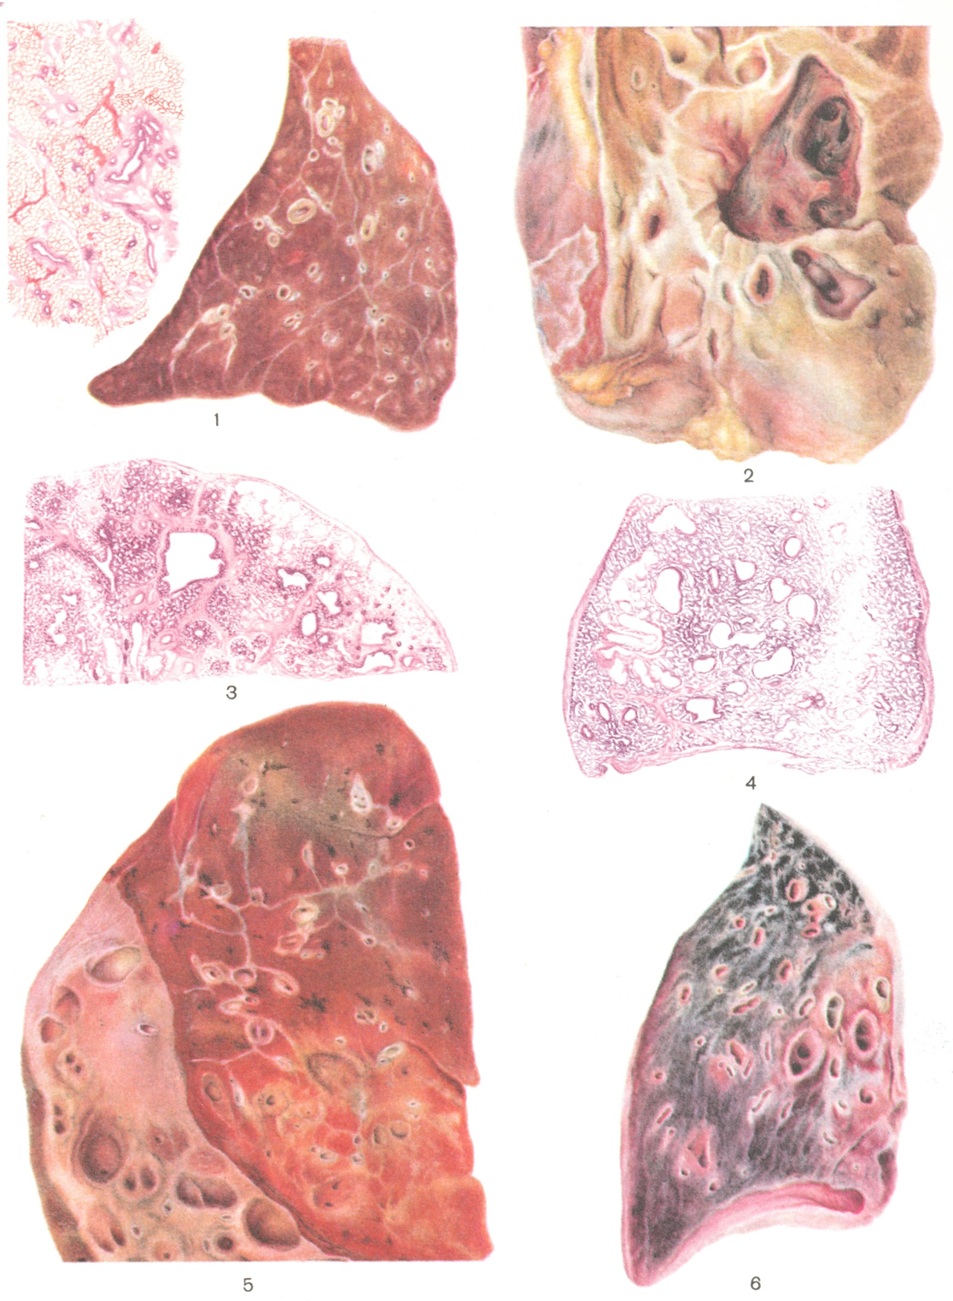

Патологическая анатомия. Макроскопически по типу расширения бронхов выделяют цилиндрические, мешотчатые, веретенообразные и чёткообразные Б., а по толщине стенок расширенных участков — атрофические и гипертрофические. Однако микроскопический анализ показывает, что в основе утолщения стенки Б. не всегда лежит гипертрофия слизистой или мышечной оболочек, она может быть обусловлена отёком, воспалительной инфильтрацией, склерозом.

Ретенционные Б. (цветн. рис. 1 и 5) чаще бывают цилиндрической или веретенообразной формы. В зависимости от патогенетического варианта и стадии развития Б. преобладают либо признаки сгущения бронхиального секрета (напр., при муковисцидозе), либо (чаще) потеря тонуса бронхиальных стенок на фоне признаков хрон. панбронхита. В последнем случае слизистая оболочка утолщена, иногда с язвеннополипозными изменениями, эпителий с явлениями регенерации, иногда метаплазии. Меняются индексы Родмана (отношение толщины слизистой оболочки к толщине всей стенки бронха) и Рида (отношение толщины слоя желез к толще всей слизистой оболочки). В норме оба индекса соответствуют 1:4. Гистохим. ШИК-реакция (реакция с шифф-йодной к-той) и реакция с толуидиновым синим выявляют нарушение секреции желёз и бокаловидных клеток. Вместо отдельных ШИК-позитивных гранул в протоплазме клеток появляется много ШИК-позитивного вещества, растягивающего всю протоплазму клеток. Слизь неоднородна по содержанию мукопротеидов и сульфатированных муко-полисахаридов. В поздние сроки железы атрофируются, кистовидно растягиваются, секрет их сгущается. Фаза гиперсекреции характеризуется резким расширением устьев желез, около последних увеличивается количество лимф, фолликулов. Лимфоидная инфильтрация делается более компактной, чем в норме, охватывает все слои стенок бронхов; между лимфоидными элементами появляется много плазматических клеток и нарастает пиронинофилия их (смотри Плазматические клетки), определяемая реакцией Браше. Реакция с толуидиновым синим вскрывает в стенках Б. большое количество тучных клеток, располагающихся по ходу расширенных бронхиальных вен и нарастающего количества артерио-венозных анастомозов. При Б. в дистальных отделах бронхов инфильтраты обычно распространяются на прилежащие стенки альвеол (перифокальная пневмония). Мышечные волокна в стенках Б. разъединены, атрофичны, количество гликогена в них уменьшено, иногда выявляется жировая дистрофия. В хрящевых пластинках обнаруживается обызвествление и развитие костномозговой ткани. Выявляется поражение нервного аппарата бронхов. В интрамуральных и прикорневых ганглиях определяется дистрофия нервных клеток, пикноз их ядер, вакуолизация протоплазмы. В нервных волокнах отмечается варикоз, зернистый распад осевых цилиндров, особенно интенсивно выраженный в толстых афферентных и эфферентных проводниках. В меньшей степени изменяются тонкие мякотные и безмякотные волокна. Нарастающие дистрофические и атрофические процессы сменяются склерозом и ведут к деформации просвета бронхов.

Деструктивные Б. (цветной рис. 2 и 3) имеют большей частью мешотчатую форму. Наблюдаются при нагноении бронха и окружающих его тканей; для их обозначения нередко употребляют термин «бронхоэктатическая каверна». Гнойное расплавление стенки сменяется развитием грануляционной ткани, заменяющей все компоненты бронхи¬альной стенки. Пневмония и склероз распространяются на окружающую альвеолярную паренхиму в большей мере, чем при ретенционных Б. В стенках таких Б. отмечаются обильные ангиоматозные структуры, служащие источником кровотечений.

Ателектатическис Б. (цветн. рис. 4 и 6) обусловлены нарастанием градиента между внутри-плевральным и внутрибронхиальным давлением при объёмном уменьшении части лёгкого. Они характеризуются равномерным распределением кистовидных расширений бронхов в зоне ателектаза. В стенках бронхов обычно хорошо различимы структурные компоненты, воспаление выражено нерезко, за исключением бронха, обтурация которого привела к ателектазу. В этом бронхе развиваются деструктивные изменения. Помимо инородных тел бронхов, к ателектатическим Б. могут привести прикорневые воспалительные процессы и склероз.

Возможны Б. вследствие порока развития бронхов (цветной рисунок 5) преипостнатального типа. Лишь первые из них могут называться врождёнными. Значительно чаще расширение просвета бронхов обусловлено присоединением инфекции к гипопластическим процессам в стенке бронха.